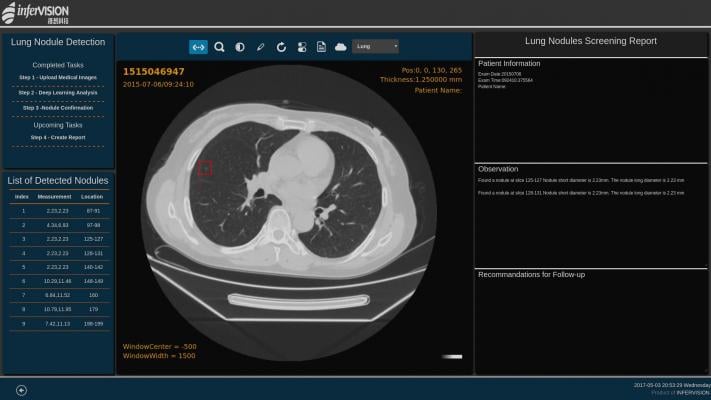

The National Evaluation System for Health Technology Coordinating Center (NESTcc) selected the “Lung-RADS Assist: Advanced Radiology Guidance, Reporting and Monitoring” use case. The center supports timely, reliable and cost-effective evidence development regarding FDA medical device pre- and post-market requirements.

Lung-RADS Assist will determine the end-to-end workflow from deployment of an AI algorithm in a radiology reporting system through capture of performance metrics within a national registry. It will:

- Utilize existing ACR technology to demonstrate the ability to collect validation data and perform local algorithm testing prior to market approval;

- Utilize existing ACR technology to facilitate interoperability between reporting and AI vendors to generate standardized data in a real-world setting; and

- Capture validation data and real-world events in a national registry to enable both facility-level and cross-facility reporting.

Use cases are clinical scenarios in which artificial intelligence (AI) use may improve care. Defining these cases is a first step in the creation of AI algorithms to answer primary clinical questions in each case. Medical imaging AI use case development is an initial focus of the ACR DSI. The DSI was launched in May 2017 to develop and use AI to help radiologists improve medical imaging care.